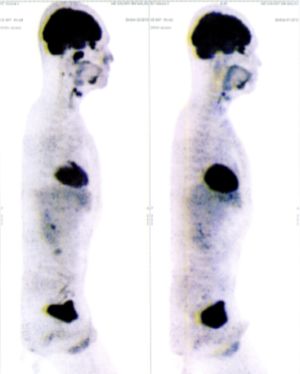

Below are some of the cases, from more than 80 cases we have treated so far with good results. When reading the PET/CT scans, the picture on the left is before treatment, and the picture on the right is after treatment. The intensity of black represents the activity of the cancer, but some black areas are not cancer: brain, heart, radioactive urine in bladder. For the heart, the intensity of black depends on the number of hours of fasting: if more than 10 hours, the heart is not even black, but if fasting is less than 6 hours, it is very black. The intensity of black in the brain can be variable in different scans depending on the brain activity at the time of the scan. The intensity of black in the radioactive urine can also be variable due to the hydration of patients and the time of injection of diuretic.

CASE NO: 1

(HEPATOCELLULAR CARCINOMA + STOMACH CANCER)

A middle-aged women who is very thin and very weak, can hardly walk, lying in bed most of the time. She saw a cancer specialist in a top hospital who discovered that she had massive hepatocellular carcinoma, and another cancer in the stomach. Given that hepatocellular carcinoma is incurable and stomach cancer is very difficult if not impossible to cure without surgery, she was told that nothing could be done for her. She came to ask us to help her. After just 4 treatment, the hepatocellular carcinoma went into remission, and the stomach cancer (arrow) became less active. Until today, more than 6 months later, the hepatocellular carcinoma is still in remission.